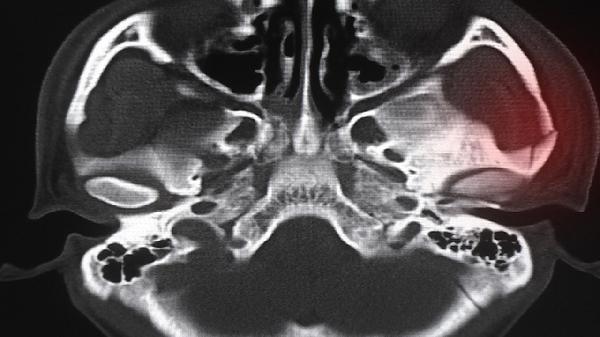

面部受到钝器击打或硬物撞击是常见原因,如拳击、棍棒伤等。外力作用于颧骨区域时,骨结构可能发生断裂或塌陷。此类损伤常伴随局部肿胀、皮下淤血,需通过CT检查明确骨折范围。

车祸中头部撞击方向盘、挡风玻璃等硬物时,冲击力可通过颧弓传导至颧骨体部。此类骨折多合并眶壁骨折或上颌骨损伤,可能出现复视、面部麻木等神经症状。

斗殴等故意伤害行为中,颧骨作为面部突出部位易受攻击。此类损伤可能伴随颧弓塌陷压迫下颌骨喙突,导致张口受限。需警惕合并颅内损伤的可能。